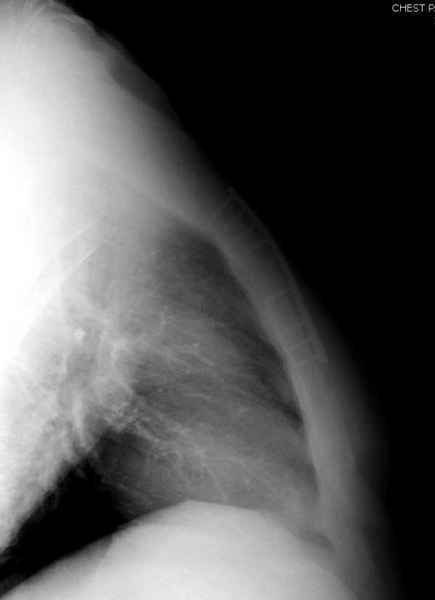

Юра, интересно, насколько такой остеосинтез контролирует степень репозиции, а то у меня имеются снимки девочки 11 лет, направленной ко мне на консультацию из одной из республик бывшего союза.

После торакальной операции, по-видимому, сильно натянули проволоку, и в результате получился захлест отломков в друг друга.

Оперировавший хирург предлагает подождать, а родителей беспокоит проблема прогрессирующей ассиметрии лица, как при кривошее.

С такими продольными несращениями мне не приходилось иметь дело, поэтому направил в один из центральных институтов детской ортопедии России.

А простые посттравматические ложные суставы грудины приходилось оперировать с ограничителем сверла и с фиксацией 2.4 мм пластинами с угловой стабильностью.